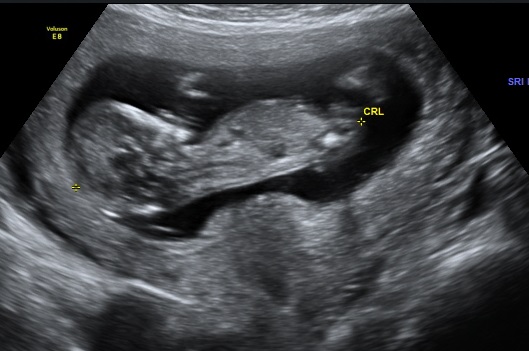

I'm new to posting on these sites, however my curiosity has the better of me so I've taken out my 13 week scan images and was hoping someone could provide me any thoughts as to whether I'm having a boy or a girl. I've read the theory on the "nub" but still cannot make out the gender with my limited knowledge.

The pictures posted below were the four best I had from the 13 week scan.

Girl. Long straight and parallel to spine:)